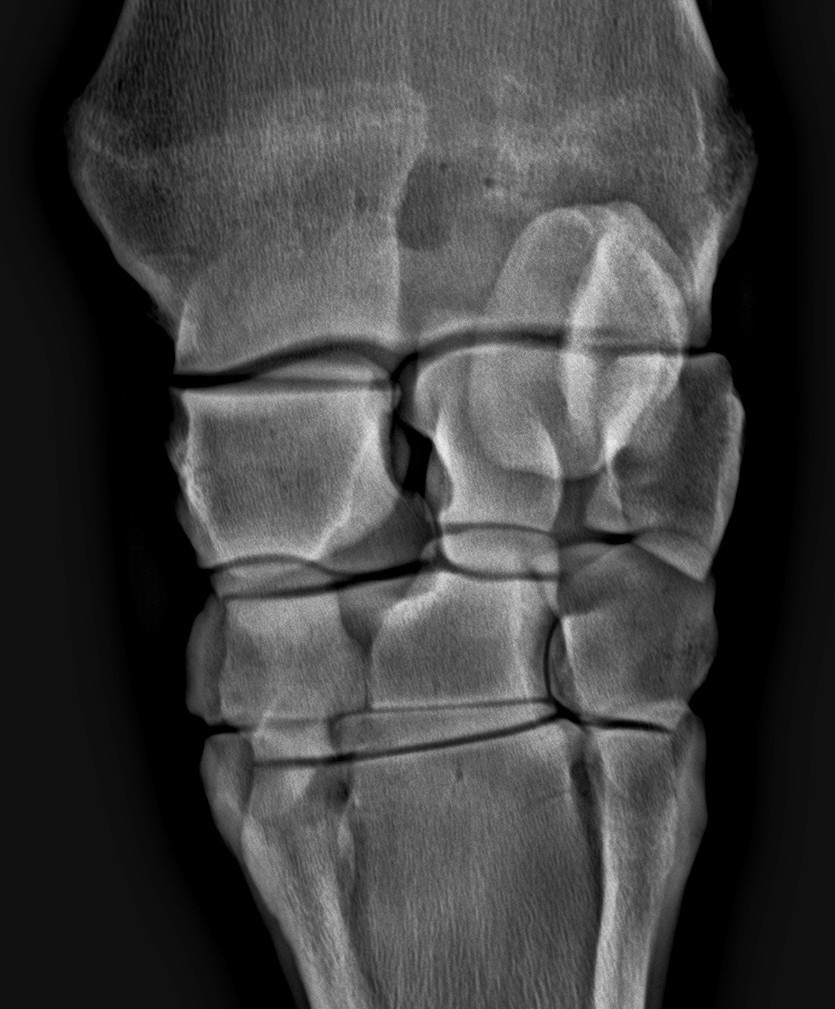

A galopp világában nagyon gyakori betegség a lábtőízület gyulladás. A fáradó, de nagyon gyorsan vágtató ló lábtövében olyan erősen nyomódnak egymásnak a porcfelszínek, hogy azok sokkal gyorsabban romlásnak indulnak, mint az egyéb munkát végző lovaknál.

A diagnózishoz a hajlítási próba-érzéstelenítés-röntgen útvonalon juthatunk el. Az ízületbe adott injekciók mellett sokszor szükséges lehet artroszkópiára is.